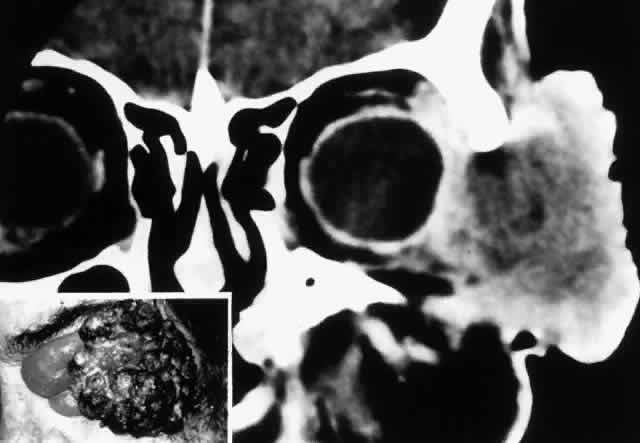

Fig. 7. A 61-year-old chronic alcoholic man presented with a fungating, putrefying, left temporal mass(inset) that extended into the adjacent orbit and flattened the globe, as shown on coronal CT scan. It proved to be a squamous cell carcinoma of the skin associated with cervical and mediastinal adenopathy. He underwent radical local radiotherapy, which led to regression of the local lesion. (Rootman J, Ragaz J, Cline R, Lapointe JS: Metastatic and secondary tumors of the orbit. In Rootman JR (ed): Diseases of the Orbit: A Multidisciplinary Approach, pp 405–427. Philadelphia, JB Lippincott, 1988.)

Fig. 8. A 73-year-old man treated 3 years previously with excision of a squamous cell carcinoma in the left supraorbital region had recurrence of tumor, which was again excised. He developed progressive pain and tingling in the forehead, vertical diplopia, and finally general malaise lasting 18 months, ultimately requiring hospitalization. He was treated with corticosteroids for presumed Tolosa-Hunt syndrome, showed minimal improvement, and was discharged. Over a 2-month period, he developed decreased vision, ptosis, and bulging of the eye. On presentation he had vision of 20/80 with a relative afferent pupillary defect. There was hypesthesia in the distribution of cranial nerve V1 and hyperesthesia in V2. He had a palpable fixed cord in the forehead in the distribution of the supraorbital nerve, complete ptosis, ophthalmoplegia, and 7 mm of proptosis (A). CT scan showed local infiltration along the supraorbital nerve (B, arrow), with extension of a soft tissue mass along the orbital roof to the orbital apex (C), through a widened superior orbital fissure, and into the cavernous sinus (D). An orbital biopsy revealed cords of squamous cells (E) (H & E, × 80) and evidence of infiltration inside a small branch nerve sheath (F) (H & E, × 80). A single fraction of 10 Gy was given as palliative treatment for pain control.